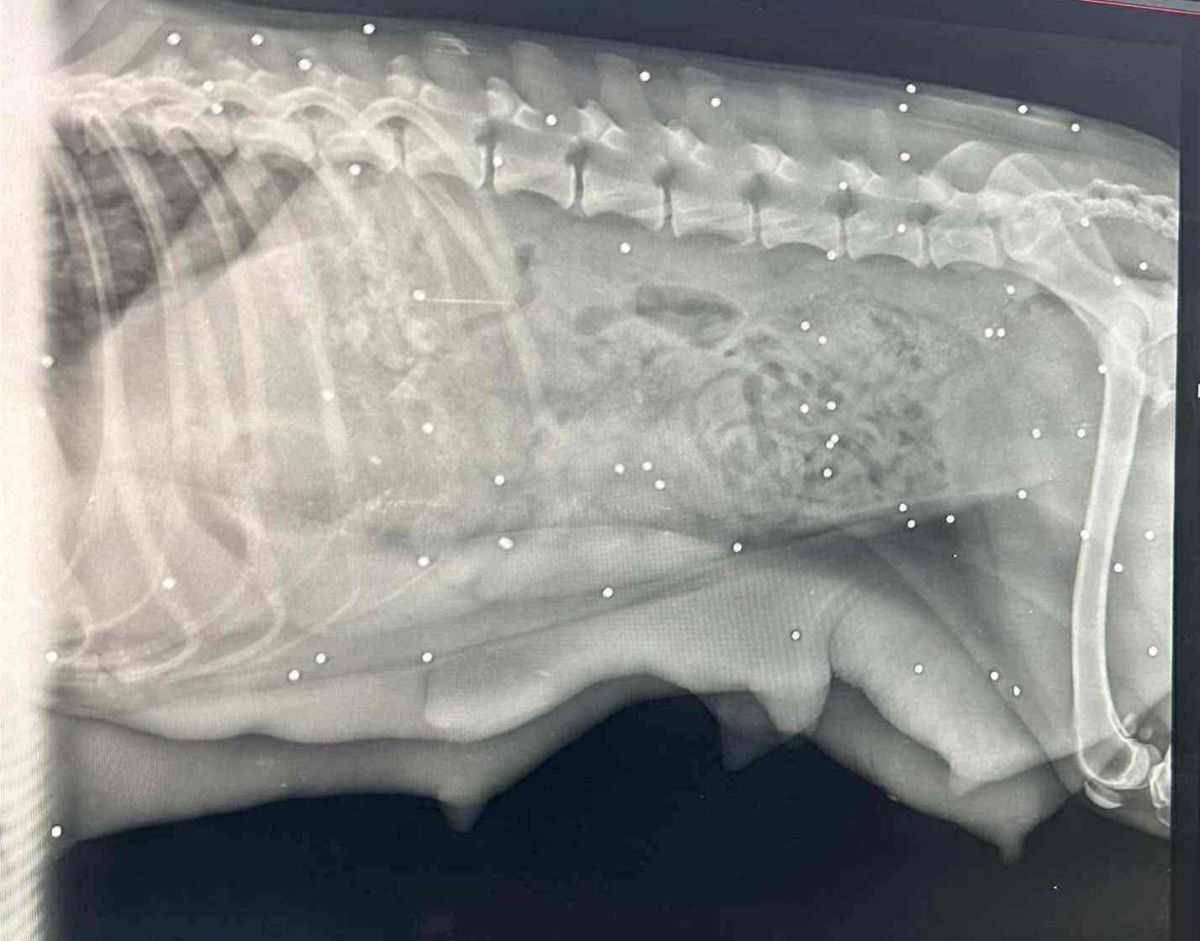

Istoga dana napravljen je i kontrolni rendgen, kako bi se isključila mogućnost da se još nije porodila. Štenaca nije bilo, ali rendgenska snimka otkrila je nešto šokantno – tijelo puno metaka.